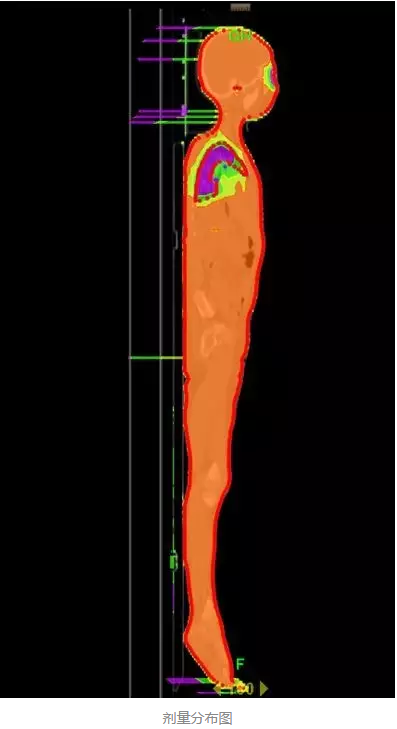

еңЁе®һйӘҢйғ‘еӨ§дёҖйҷ„йҷўйҰ–дҫӢ TBI зҡ„еҺҶзЁӢдёӯ����пјҢж”ҫе°„жІ»з–—йғЁжқҺеӣҪж–Үдё»д»»и®Өзңҹ TBI зҡ„ж•ҙдёӘжүӢиүәжөҒзЁӢ����пјҢйғӯи·ғдҝЎеүҜдё»д»»иҜҰз»Ҷи®Өзңҹе®һйӘҢдёҺеҢ…з®Ў����пјҢеҢ»з”ҹз»„еј ж—ӯдёңеҢ»з”ҹйҳ…иҜ»зӣёе…іж–ҮзҢ®����пјҢ并дәІиҮӘеҲ°ејҖеұ•иҜҘжүӢиүәйўҶе…Ҳзҡ„е№ҝе·һеҶӣеҢәжҖ»еҢ»йҷўж”ҫ疗科еӯҰд№ ����пјҢиҜҘйҷўж”ҫ疗科й»Һйқҷдё»д»»зҡ„ж”ҫз–—еӣўйҳҹз»ҷдәҲдәҶж— з§Ғзҡ„йјҺеҠӣеӨ§дёҫиө„еҠ©���пјӣзү©зҗҶз»„з»„й•ҝ马йҳіе…үеҗ‘еҜјзү©зҗҶз»„е…ЁдҪ“иҒҢе‘ҳиө·еҠІеҚҸи°ғ����пјҢзҺӢжө·жҙӢзү©зҗҶеёҲдҪҝз”Ёе‘ЁеӨ©дј‘жҒҜзҡ„ж—¶й—ҙдёҫиЎҢиҙЁйҮҸжҺ§еҲ¶жқҘзЎ®���пјӣйўҠе’§зҳҹзІ•зі»йӮЈеҜ°���пјӣжүӢиүәз»„з»„й•ҝжӣ№дҝҠеҚҺеҗ‘еҜјжүӢиүәз»„е…ЁдҪ“жҲҗе‘ҳж”»еқҡе…Ӣйҡҫ����пјҢжңҖз»ҲеңЁеҗ„дёӘйғЁеҲҶзҡ„й…ҚеҗҲиө·еҠІдёӢ����пјҢ2016 е№ҙ 5 жңҲ 16 ж—Ҙйғ‘е·һеӨ§еӯҰ第дёҖйҡ¶еұһеҢ»йҷўйҰ–дҫӢ TBI жІ»з–—е®ҢжҲҗ����пјҢз”ұдәҺж”ҫе°„жІ»з–—йғЁдҪҝз”Ё TOMO HD еҠ йҖҹеҷЁе®һйӘҢзҡ„ TBI ����пјҢеүӮйҮҸжј«иЎҚеҚҒеҲҶе®Ңе–„пјҲеҰӮдёӢеӣҫжүҖзӨәпјү����пјҢзұ»дјјй•ҢеҲ»����пјҢд»ҘжҳҜеҸҲиў«з§°дёәгҖҢй•ҢеҲ»ејҸе…Ёиә«ж”ҫз–—гҖҚ����гҖӮ